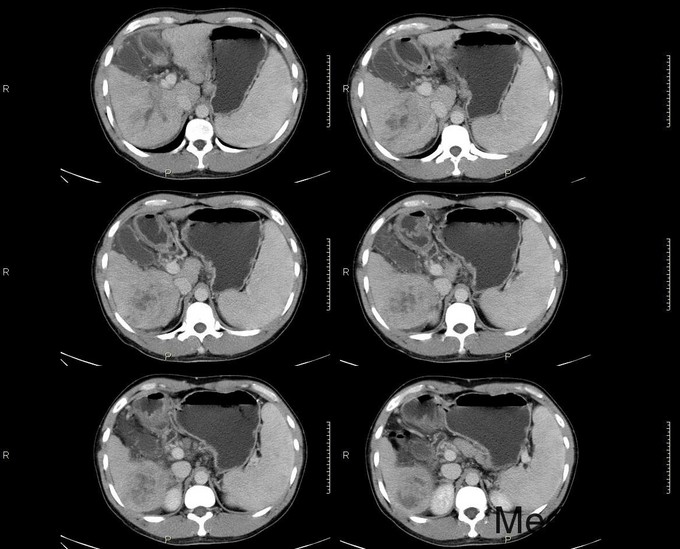

主诉:反复乏力、纳差2月余。身目黄染1月余。 病史:患者中老年男性,2月前出现乏力、纳差,查乙肝两对半示大三阳,上腹部CT示肝硬化,予护肝等治疗后好转出院。1月前天前出现身目黄染,伴瘙痒,再次入院。 既往史:患者有肝癌家族史(父亲肝癌去世)

查体:慢性肝病体征,肝掌阳性,蜘蛛痣阳性,胸前毛细血管扩张,腹水征阳性,肝脾肋下可触及。 辅查:生化:谷草146,谷丙110,总胆184,直胆114,白蛋白38,凝血四项:PT17.9s,PTA56。 CA-125: 600,CA-199:54.13,AFP:98.73。 肝彩:1、肝硬化,肝左叶可见高回声团。 上腹部CT: 肝癌、肝硬化、脾大

诊断:1、原发性肝癌;2、乙肝肝硬化 1、常规护肝退黄降酶,输血浆,护胃制酸等对症支持治疗 2、转肝脏外科。